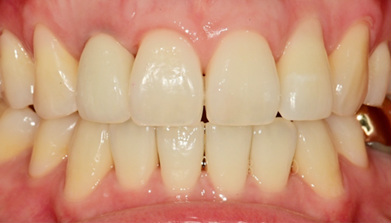

임플란트를 식립하고 동시에 보철물도 완성해드립니다.

내원 당일 이루어지는 임플란트 기술력! 하루 완성 임플란트는 당일에 식립하고

임시 보철물까지 완성됩니다.